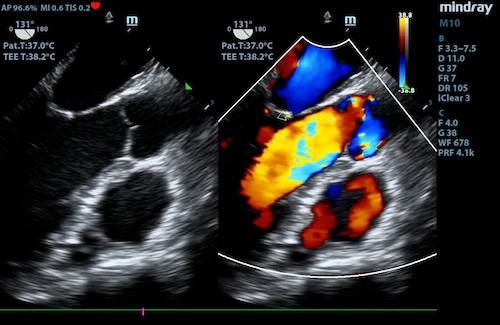

A phased transducer has a small footprint with a sector image shape and features high temporal resolution and penetration. This allows clinicians to image structures that are moving in real-time. Phased transducers are most frequently used with applications ranging from cardiac, transcranial, abdomen, and pediatrics.

Apical 4 chamber with color Doppler using a phased array transducer

Transesophageal Echo Transducers

A transesophageal Echo (TEE) transducer is a specialty transducer used to image structures from inside the body. It is designed to be inserted into the esophagus and image the heart from behind. This offers the ability to image structures that cannot be well visualized in a transthoracic echo – TEE imaging offers an unobstructed view of the heart (i.e., lungs and ribs do not get in the way). The image will be a sector shape that offers a wide field of view. TEE transducers are used exclusively for cardiac imaging.

Heart visualized with TEE transducer